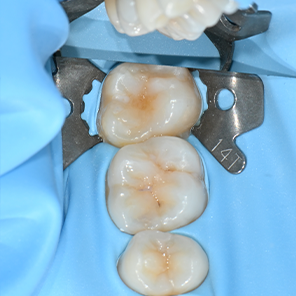

연세일등치과는 만족스러운 수복 결과를 위해, 치료 환경(러버댐)과 신중하게 재료를 선택하는 것, 두 가지를 모두 중요하게 생각합니다.

01. 치료 환경

치과 수복 과정에서 결과의 지속성을 좌우하는 중요한 요소 중 하나는

바로 건조 환경의 유지입니다. 연세일등치과는 레진빌드업 시 러버댐(Rubber Dam)

사용을 원칙으로 삼아, 수복물과 치아의 안정적인 결합을 방해할 수 있는 침(타액)과

미세한 습기, 이물질로부터 치료 부위를 보호합니다.